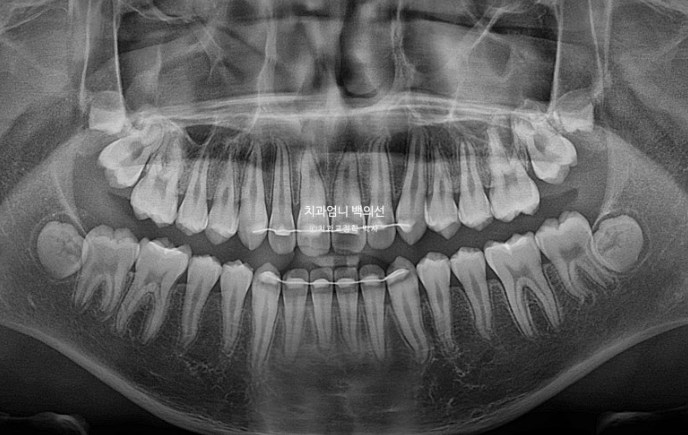

치근평행도는 좋고 치근흡수는 없습니다.

치아 이동속도는 빠르고 교정 부작용이 적은 것은 어린이교정의 큰 장점입니다.